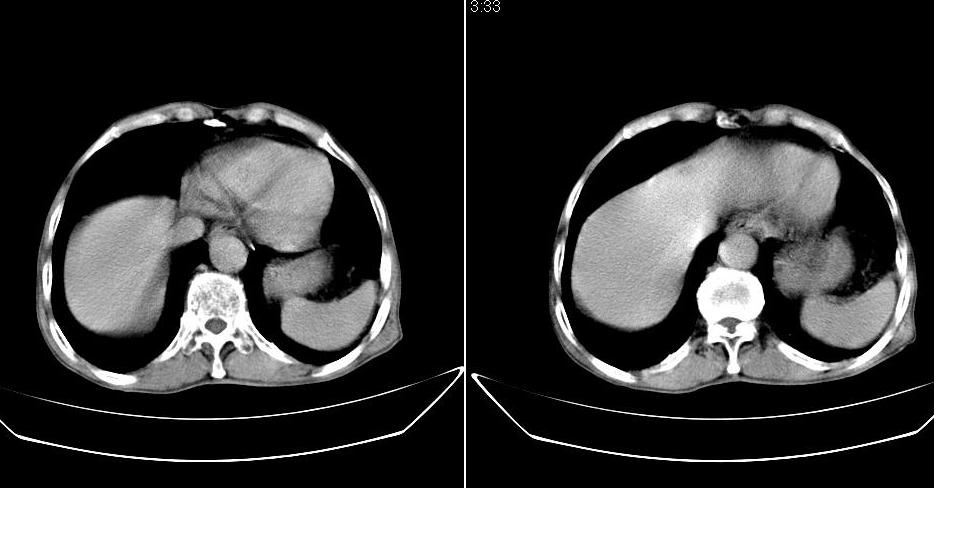

男,76岁,上腹部疼二天来就诊,彩超提示肝左叶占位,随后做上腹部ct平扫,今天做上腹部ct增强扫描,手工推药,效果不好,请谅解。

肝左叶s4肿块强化形式大概是:慢进慢出,逐渐强化----考虑血管瘤/腺瘤?{动脉期应更提前扫}。

肝右叶前段hcc

1)肝右叶前段低密度灶,不排除肝癌可能;建议查afp。2)右肾上极囊肿。

肝内胆管积气扩张,胆囊增大,肝右前叶低密度灶,逐渐强化,一元论,胆系感染,局限性肝脓肿;右肾囊肿。

考虑肝s4段肝脓肿可能?未排除肝癌。右肾上极囊肿。